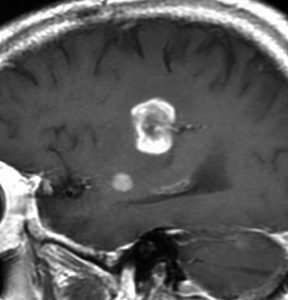

60代の患者さんの右前頭葉深部から島回に発生したものです。初発症状は症候性てんかんです。

ガドリニウム増強される腫瘍の中心部に壊死があり,悪性神経膠腫としては腫瘍周囲浮腫が強すぎるように見えるので,リンパ腫 PCNSLに似た画像所見です。